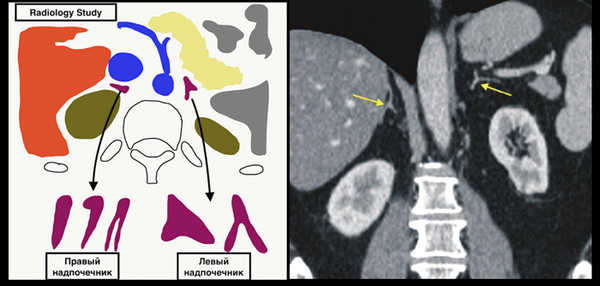

(Слева) На рисунке показана типичная анатомия надпочечников. Обратите внимание на множественные источники кровоснабжения. Венозный отток от правого надпочечника осуществляется через надпочечниковую вену непосредственно в НПВ, в то время как левая надпочечниковая вена впадает в почечную вену.

(Справа) Правый надпочечник прилежит к НПВ, расположен латеральнее правой диафрагмальной ножки и медиальнее печени. Левый надпочечник обычно расположен вентрально по отношению к верхнему полюсу левой почки и позади селезеночной вены. Левый надпочечник выглядит в виде перевернутой «Y», а правый больше напоминает перевернутую «V». (Слева) На рисунке показана стимуляция передней доли гипофиза адреналином и цитокинами, гормонами гипоталамуса — кортиколиберин-рилизинг-гормоном (КРГ) или антидиуретическим гормоном (АДГ). Это приводит к высвобождению АКТГ, что вызывает секрецию кортизола надпочечниками. Избыточный уровень циркулирующего кортизола в крови ингибирует дальнейшую гипофизарную секрецию.

Анатомия: положение

- Поскольку надпочечники погружены в жир забрюшинного пространства, они отчетливо визуализируются при KT почти у каждого пациента, но нередко сливаются с изображением печени и с капсулой почки. Оба надпочечника локализуются в верхней части параренального пространсгва и окружены ренальной фасцией.

- Правый надпочечник занимает переднемедиальное положение относительно верхнего полюса правой почки и находится несколько выше нее, в углу между правой долей печени и правой ножкой диафрагмы, сразу позади нижней полой вены.

- Левый надпочечник располагается позади и латерально от аорты и расположен больше спереди и медиально, чем выше верхнего полюса левой почки. Иногда нижний полюс надпочечника располагается очень близко к сосудистой ножке почки.

Анатомия: форма

- Аксиальные КТ-срезы через надпочечники показывают, что каждый из них состоит из тела и двух ответвлений (ножек).

- Правый надпочечник обычно отображается в виде линии или напоминает по форме запятую или имеет V-образную форму, тогда как левый надпочечник чаше треугольной или Y-образной формы. Контуры надпочечника слегка вогнутые и четкие. Иногда при МСКТ с контрастированием дифференцируют кортикальный и медуллярный слои надпочечников.

- Вертикальный размер надпочечников достигает 4-6 см, ширина их - 2—3 см. Ножки имеют толщину 6-8 мм. Измерение желез не имеет значения вследствие широко варьирующих в норме размеров этих органов. Более важны для диагностики качественная оценка формы, размеров и контуров.